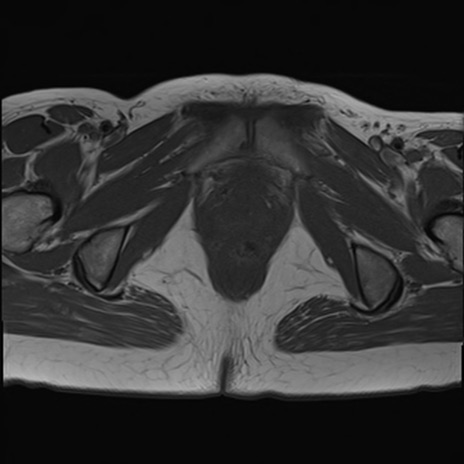

症例39 T1WI(横断像)

MRI(4日後)